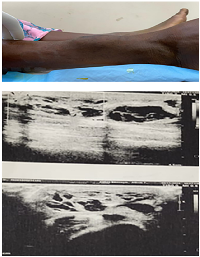

Examination revealed a firm, non-tender, relatively immobile swelling measuring approximately 6 × 5 cm, located on the anterior aspect of the lower third of the right leg. The overlying skin appeared normal, without redness, hyperpigmentation, ulceration, or prominent superficial veins. No regional lymphadenopathy was detected. Routine hematological parameters were within normal limits. Ultrasound of the swelling showed a well-defined, hypoechoic, cystic lesion measuring 6.8 × 5 cm containing internal echoes consistent with blood, suggestive of an organized hematoma (Figure 1). Fine-needle aspiration cytology (FNAC) yielded red blood cells, further supporting this initial impression.

Figure 1

Figure 1: Swelling over anterior aspect of right leg; USG showing hypoechoic cystic lesion measuring 6.8 × 5 cm containing blood as content suggestive of an organised hematoma.